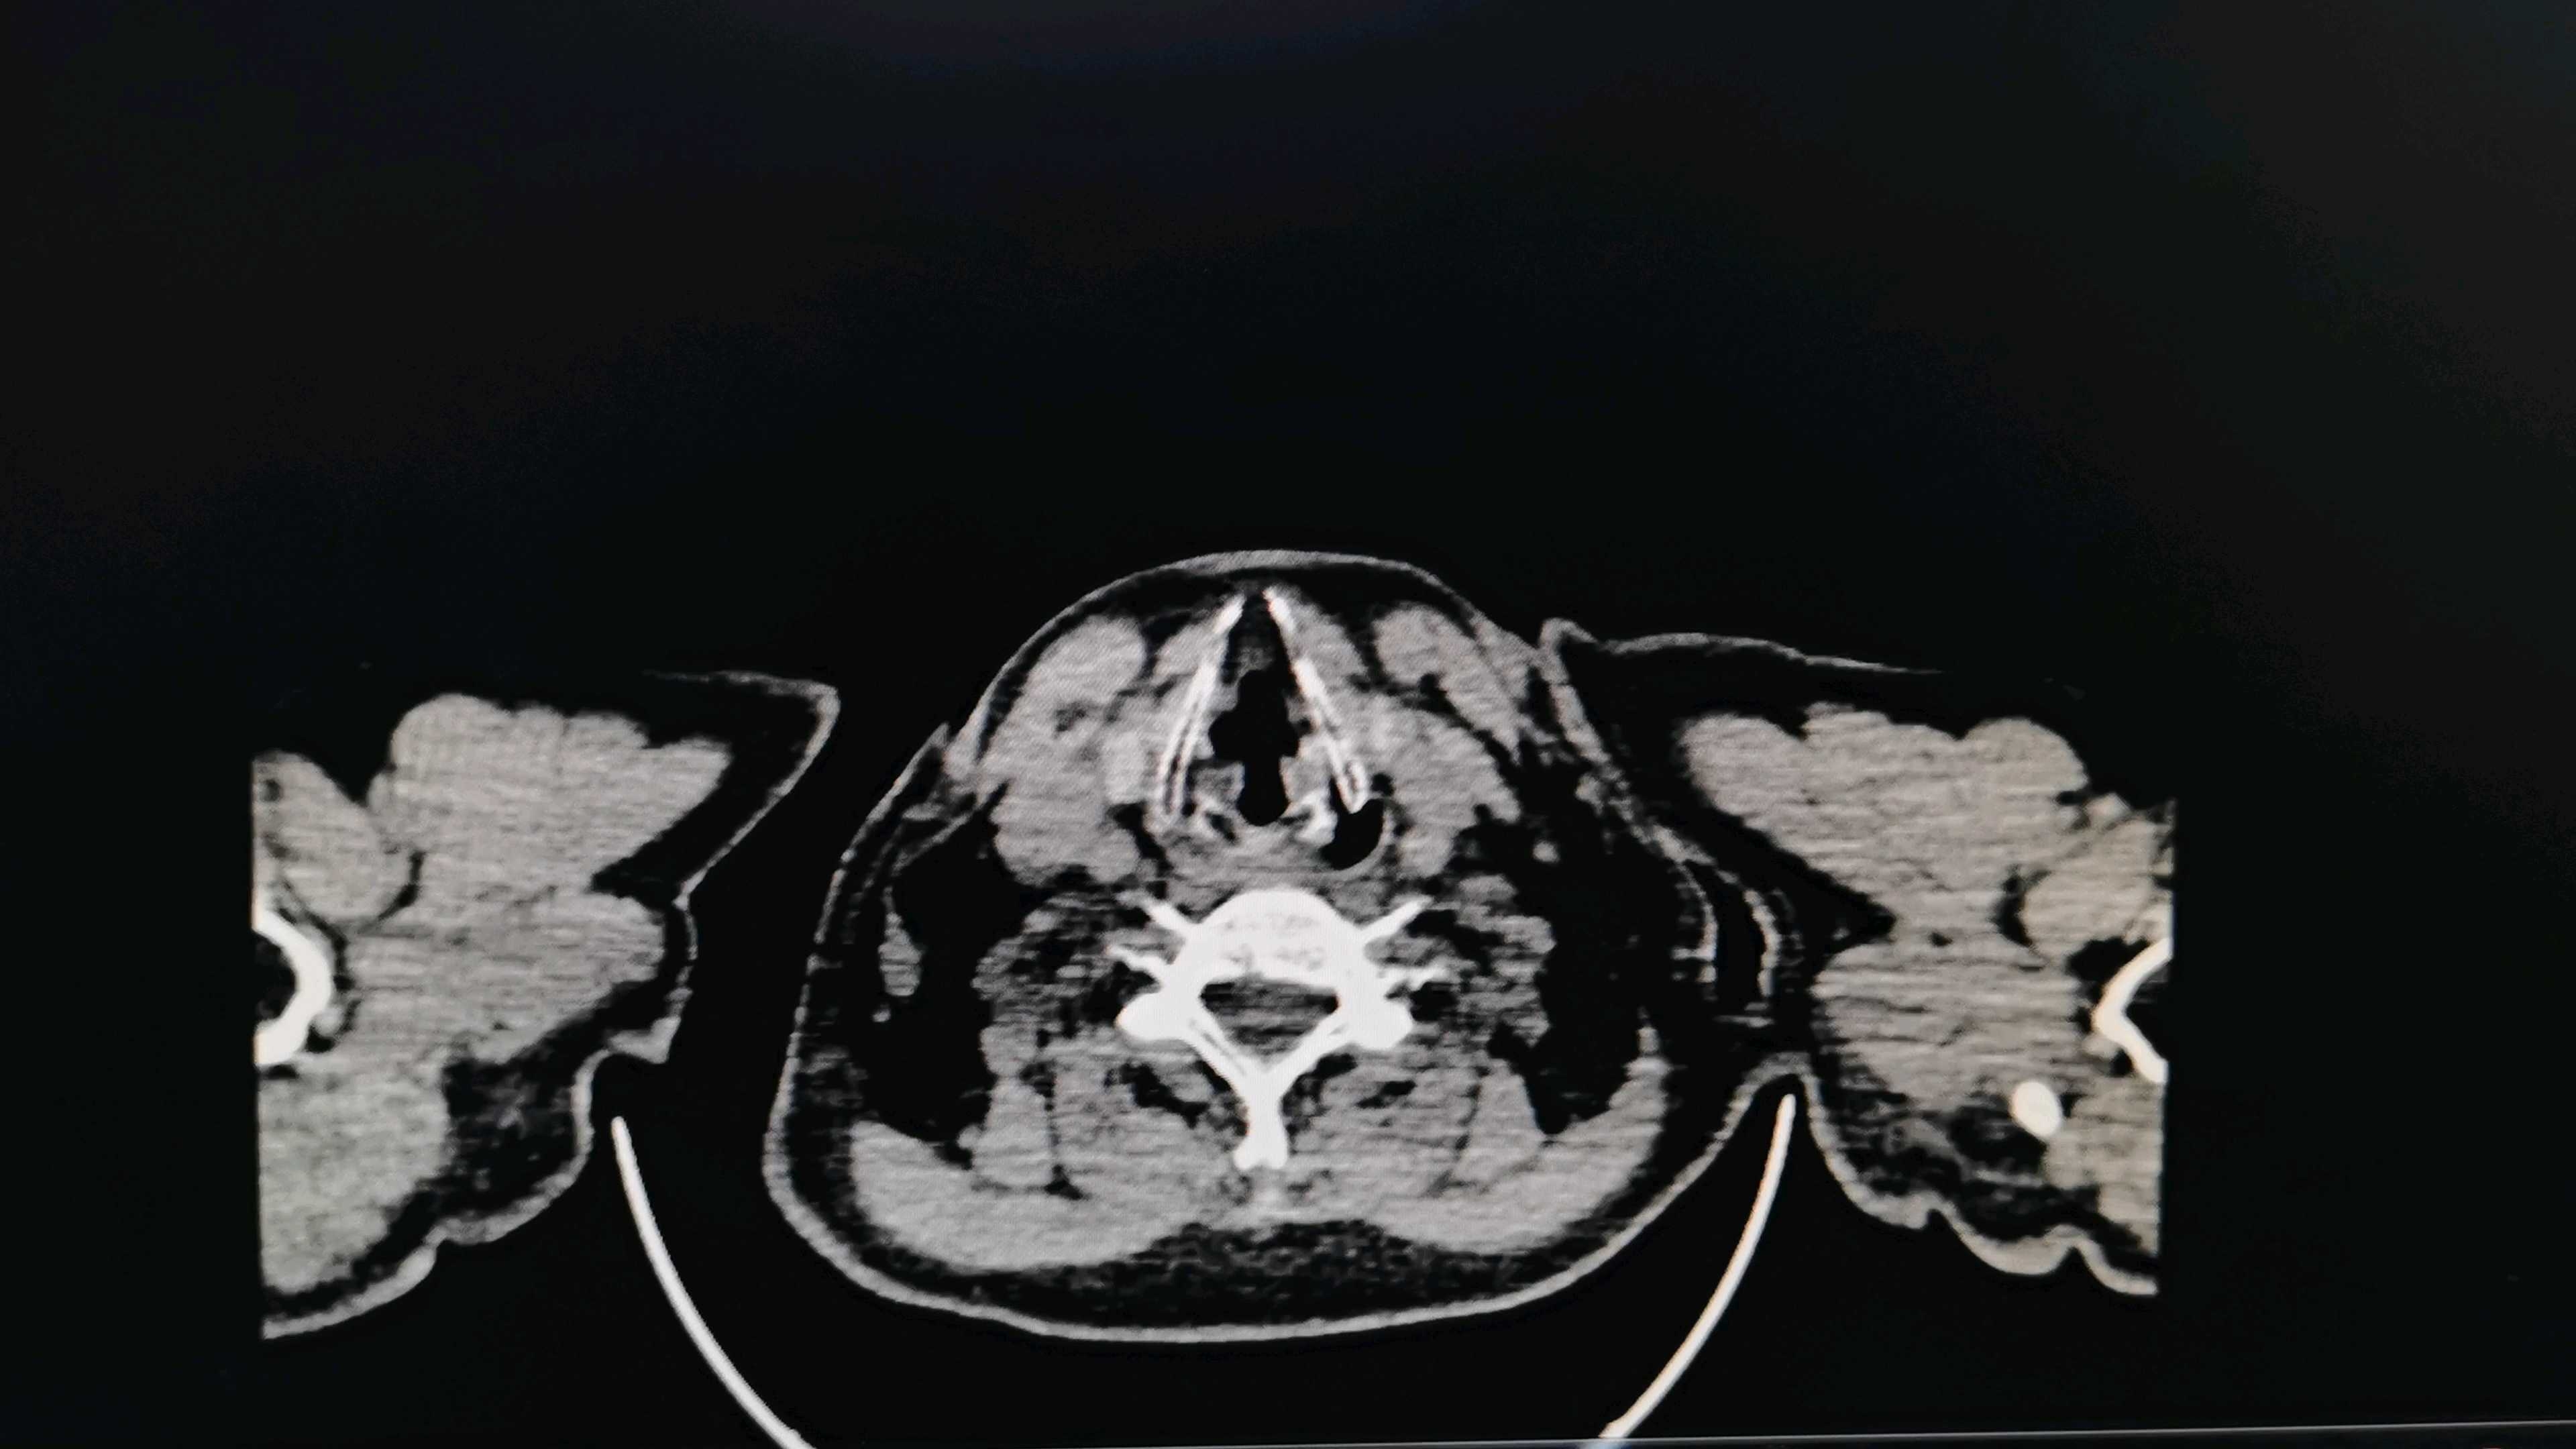

23年8月25号肺部CT片对比↓

1.空洞是什么导致的?我还需要做什么检查帮助诊断?请各位老师指教

这算气液胸?液体看着像在空洞里和空洞外?

2.有没有可能是癌性空洞?